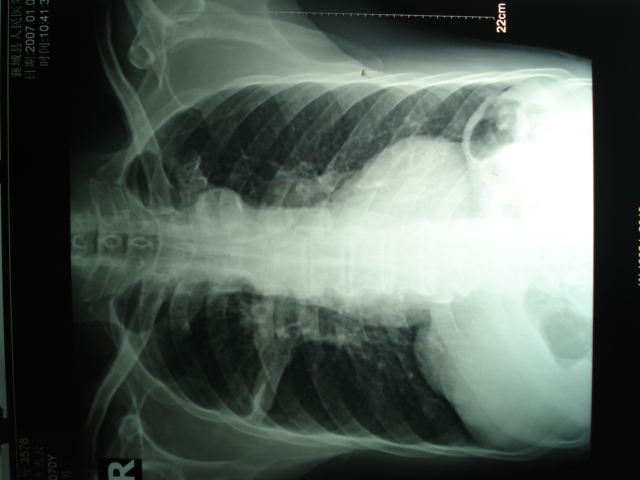

以下是引用狙击手在2007-4-18 20:17:00的发言:[br]原:2007/1/22号ct片:右肺上叶可见片状、云雾状高密度影,右肺上叶后段可见三角形高密度影,尖端指向肺门,右肺上叶后段支气管壁不规则增厚,管腔不规则增厚,纵隔未见肿大淋巴结.[br] 今ct:右肺上叶片状影增大,右肺上叶后段不张及右肺上叶后段支气管壁不规则增厚未见变化,右肺下叶背段支气管壁不规则增厚.[br] 如果考虑肺结核,但从临床证据看竟然没有一项支持肺结核,不知患者是否已经过正规抗结核治疗。没有的话,3个月了前后片看起来变化不大,似乎有不太符合肿瘤征象,不知患者是否抗炎治疗过,下叶支气管增粗还是要高度警惕,同意楼主意见,将常规病理,生化检查再做一遍。[br]

以下是引用狙击手在2007-4-18 20:17:00的发言:[br]原:2007/1/22号ct片:右肺上叶可见片状、云雾状高密度影,右肺上叶后段可见三角形高密度影,尖端指向肺门,右肺上叶后段支气管壁不规则增厚,管腔不规则增厚,纵隔未见肿大淋巴结.[br] 今ct:右肺上叶片状影增大,右肺上叶后段不张及右肺上叶后段支气管壁不规则增厚未见变化,右肺下叶背段支气管壁不规则增厚.[br] 如果考虑肺结核,但从临床证据看竟然没有一项支持肺结核,不知患者是否已经过正规抗结核治疗。没有的话,3个月了前后片看起来变化不大,似乎有不太符合肿瘤征象,不知患者是否抗炎治疗过,下叶支气管增粗还是要高度警惕,同意楼主意见,将常规病理,生化检查在做一遍。[br]